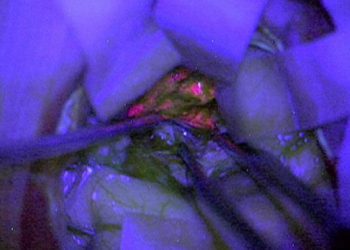

By using a chemical ALA-5, brain tumors can now be identified without much hassle.